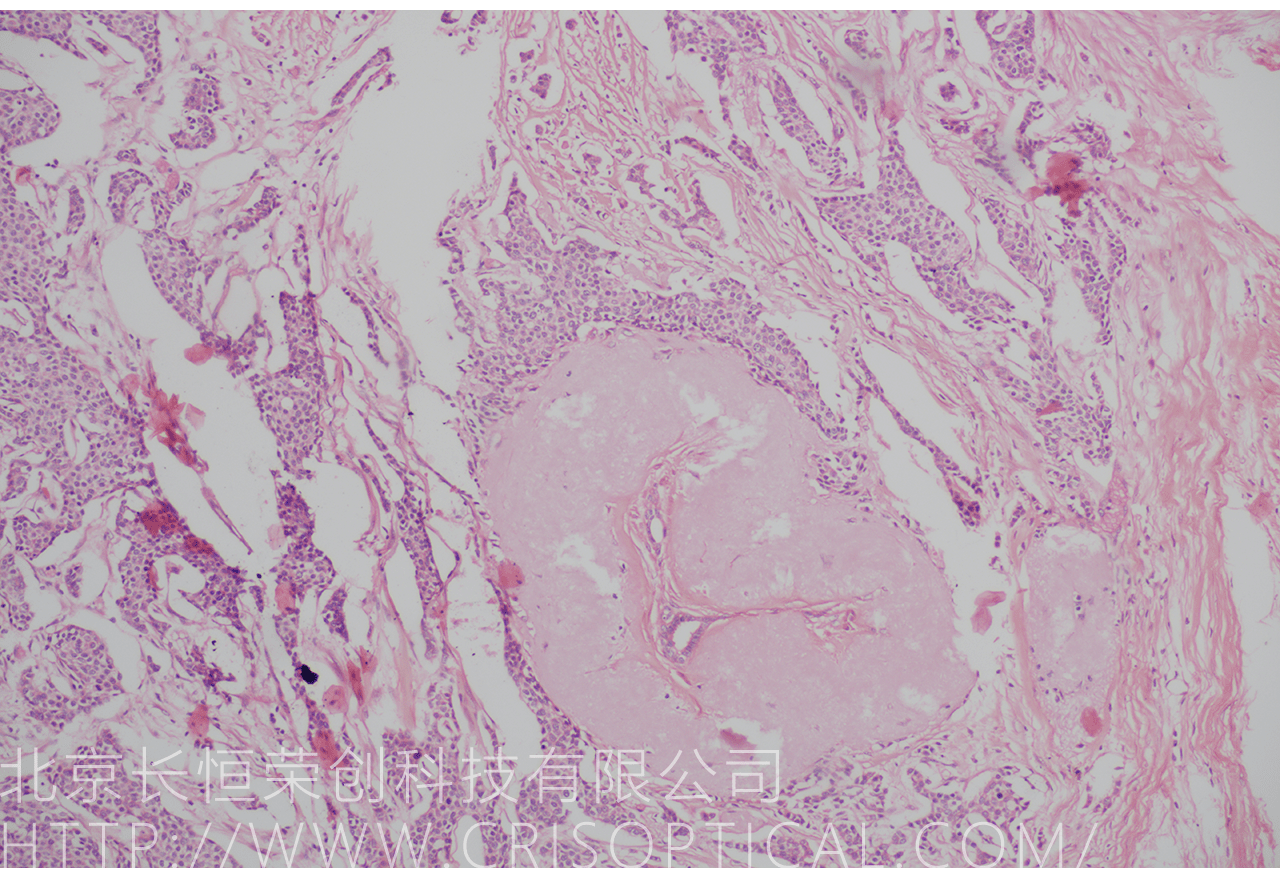

腫瘤診斷:對(duì)癌癥和其他腫瘤的病理切片觀察是確定腫瘤類型、分級(jí)和分期的關(guān)鍵步驟。醫(yī)生通過觀察組織樣本中的細(xì)胞形態(tài)、核形狀、分裂活性和其他特征,可以識(shí)別腫瘤的類型,幫助決定治療方法。